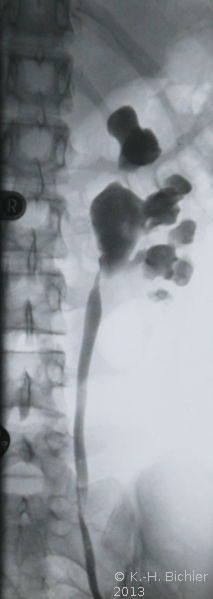

- Abbildung: Ureterabgangsstenose links bei 15jährigem Mädchen

- a) Retrograde Sondierung links: Ureterabgangsstenose präoperativ